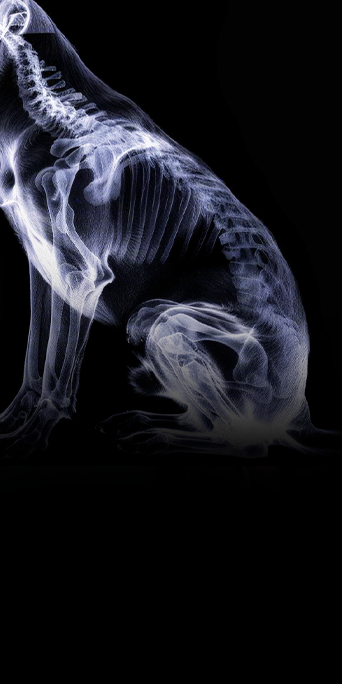

O curso “introdução ao tratamento das doenças compressivas da coluna de cães” foi criado para ajudar médicos veterinários e estudantes a compreender, com clareza e segurança, os fundamentos do exame neurológico, a localização da lesão e as principais apresentações do disco intervertebral que podem levar à compressão medular.

Sob a orientação de professores renomados da ANCLIVEPA-SP, você será guiado por conceitos indispensáveis para a rotina clínica: como interpretar sinais neurológicos, diferenciar os tipos de protrusões e extrusões discais, e entender os acessos cirúrgicos ao canal vertebral.

O curso é 100% online e dividido em três módulos essenciais: exames neurológicos e localização das lesões, tipos de lesões do disco invertebral e acesso ao canal vertebral.